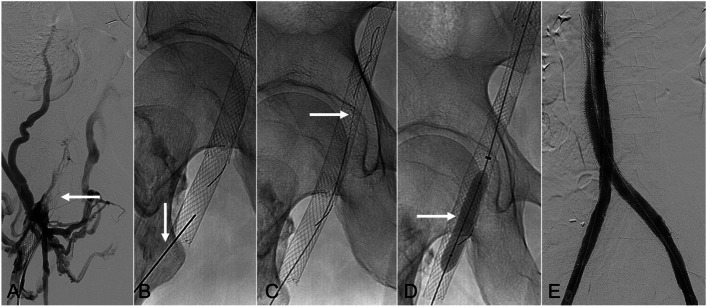

Direct percutaneous puncture of occluded venous stents as an adjunctive technique to restore patency.